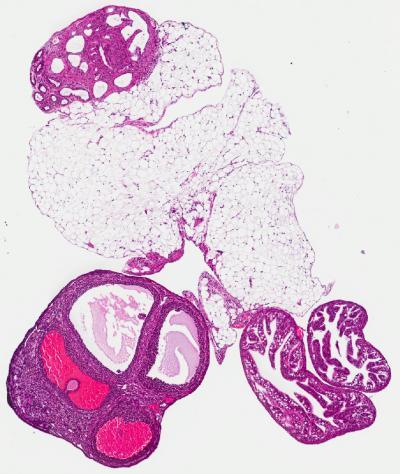

This is a mouse ovary along with the fallopian tube and some fat tissue. The tissue exhibits potentially pre-cancerous/abnormal changes.

(Photo Credit: Caitlin Brown/Freiman lab/Brown University)